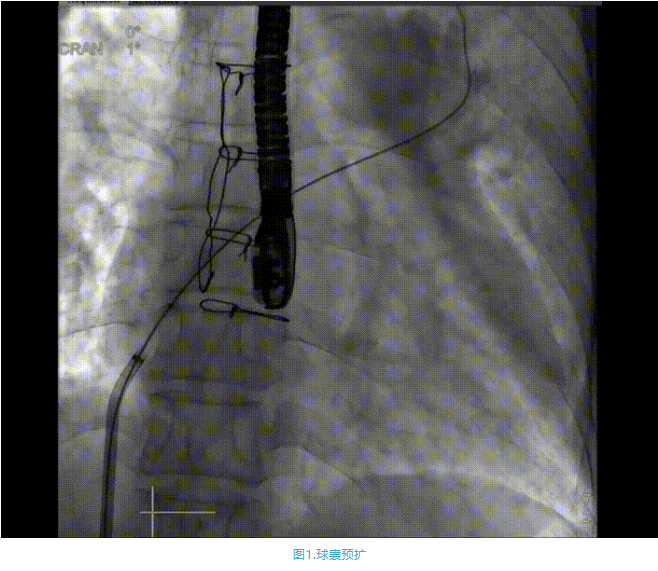

術(shù)中首先在局麻下穿刺股動(dòng)脈、股靜脈,完成心導(dǎo)管檢查評估后轉(zhuǎn)為全麻,在食道超聲引導(dǎo)下穿刺房間隔,穿刺成功后將加硬導(dǎo)絲送入左上肺靜脈建立軌道,根據(jù)患者病情行球囊預(yù)擴(kuò)張后植入6mm孔徑房間隔造孔支架,經(jīng)透視及食道超聲評估支架左右盤展開良好,夾持于房間隔兩側(cè),固定穩(wěn)定、位置良好,食道彩超顯示房水平右向左為主分流,分流孔直徑符合預(yù)期大小,心導(dǎo)管檢查評估達(dá)到預(yù)期效果,釋放造孔支架。術(shù)后12h患者下床活動(dòng),恢復(fù)順利,擬于近日完善術(shù)后評估后出院。